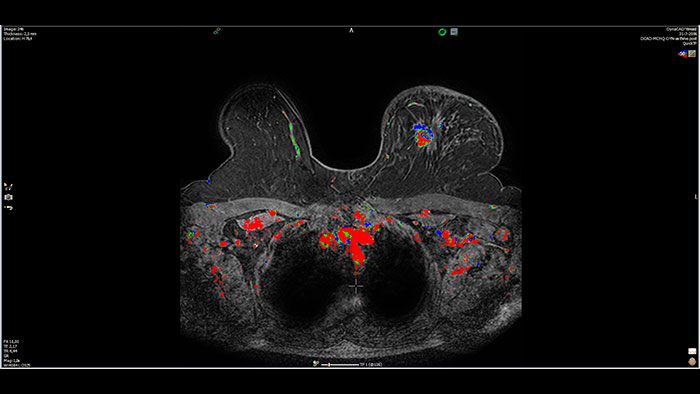

DynaCAD Breast

MR DynaCAD Breast*

Next generation of breast care

Tailored to enhance the review and analysis of MRI breast studies by providing a flexible workspace with custom hanging protocols and multi-vendor** viewing capabilities. DynaCAD’s automatic segmentation allows on-the-fly user modification and provides volume analysis, lesion composition statistics, histograms, and a 3D rendered morphological overview.

Benefits

• Results are automatically incorporated into standardized reports.

• The DynaLOC Breast Interventional Planning software module offers visual guidance for planning MR-guided breast biopsy procedures.

* Not available for sale in all countries. Please contact local Philips representative for details. This functionality is not available in IX Workstation configuration.

** Please contact a local Philips representative for details on multi-vendor coverage.

DynaCAD is a registered trademark of Invivo Corporation.